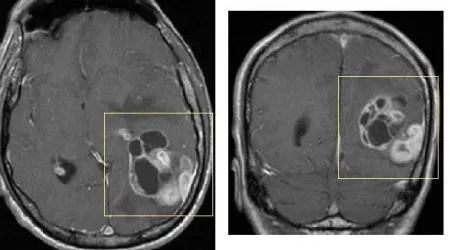

神经胶质瘤(画框所示)的MRI影像学图片

头颅CT是筛查颅内病变的“第一道屏障”。通常,在CT发现异常情况后,医生会建议患者接受头颅磁共振(MRI)检查。

目前认为,MRI是确诊脑胶质瘤的主要检查手段。若MRI仍然难以确诊,PET/CT是一个很好的补充检查措施。